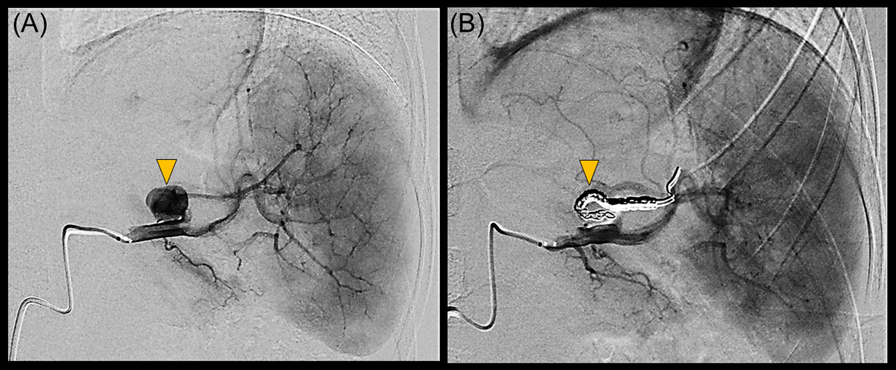

Transthoracic echocardiography revealed multiple vegetations in the aortic arch (Fig. 1). Thoracic contrast-enhanced CT indicated not only SVAS but also stenosis at the origin of either the brachiocephalic artery or the left common carotid artery (Fig. 2). At the time of admission, the patient also experienced left-sided abdominal pain and nausea. Abdominal contrast-enhanced CT revealed renal and splenic infarctions without any arterial aneurysm (Fig. 3). Magnetic resonance imaging (MRI) revealed a very small brain hemorrhage scar. Blood culture detected Abiotrophia defectiva, an endemic oral bacterium that shows penicillin sensitivity. We made a diagnosis of IE according to the modified Duke criteria.4) Urgent surgery for removing vegetations was performed to avoid cerebral embolisms, followed by antibiotic therapy using both penicillin 300,000 U/kg/day and Gentamycin 3 mg/kg/day.

Fig. 2 (A) Reconstructed images of enhanced computed tomography show supravalvar aortic stenosis and stenoses at the origins of the brachiocephalic and the left common carotid arteries. The Dotted line indicates the axial cross-section in which the lumen of the left common carotid artery is narrowing (arrow head) (B)

BCA, brachiocephalic artery; LCCA, left common carotid artery; LSA, left subclavian artery; SVAS, supravalvar aortic stenosis; SVC, superior vena cava.